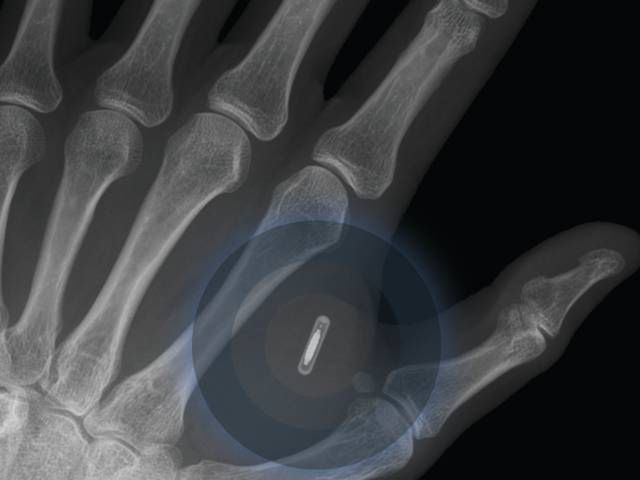

/ 8Pierwszy implant telefoniczny w 2025 r.

Za dekadę takie urządzenia pojawią się w sprzedaży. Pomogą m. in. monitorować stan zdrowia.